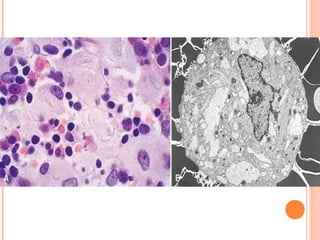

   These phagocytes (Gaucher cells) become

enlarged, with some becoming as large as 100

μm, because of the accumulation of distended

lysosomes, and develop a pathognomonic

cytoplasmic appearance characterized as

"wrinkled tissue paper"

 Affected cells appear swollen, possibly foamy

Electron microscopy reveals a whorled

configuration within lysosomes